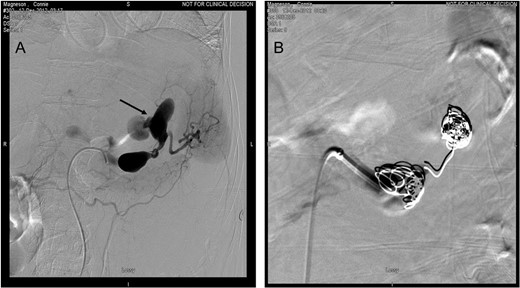

A 65 -year-old woman with a known history of multiple splenic and hepatic aneurysms was admitted to our hospital in October 2012 with acute abdomen. Abdominal computed tomography angiography showed rupture of splenic aneurysm with active extravasation of contrast and associated large left upper quadrant hematoma with small hemoperitoneum (Fig. 1). Visceral angiogram confirmed the presence of three fusiform aneurysms involving midsplenic artery (Fig. 2). The distal most aneurysm demonstrated large extravasation (Fig. 3). Coil embolization of the proximal and midsplenic artery aneurysm was performed using multiple Nester coils (Cook Medical, USA) with cessation of antegrade flow (Fig. 4). Attempt to access distal portion of the splenic artery was unsuccessful. She recovered well and was discharged 4 days later. In December 2016, she was admitted with dyspepsia and severe iron deficiency anemia requiring blood transfusion. A colonoscopy and upper endoscopy were performed which showed the presence of metallic coils in the stomach (Fig. 5). The patient subsequently underwent a combined upper endoscopy and laparoscopy. Three 5 mm ports were used to expose the lesser sac in event of hemorrhage during extraction of the coil endoscopically. An atraumatic bowel clamp was placed distal to the Treitz ligament to prevent insufflation of the small bowel. Upper endoscopy was performed using CO2 insufflation and the Nester coils were retrieved using rat tooth forceps (Fig. 6). There was no bleeding in the lesser sac after removal of the coils. A leak test was performed to rule out gastric perforation. She had an uneventful recovery and was discharged the next day.

(A) Visceral angiography revealed extravasation from distal saccular aneurysm (arrow). (B) Embolization of the aneurysm was done by using Nester coils.